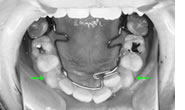

治療開始時年齢は6歳半でしたが、永久歯は1本もありませんでした。右上の乳歯Dから左上の乳歯Cまでが反対咬合の状況でした。

レントゲンの検査、家族暦などから骨格的な下顎前突の程度が大きいことがわかりましたので、オトガイ帽装置(チンキャップ)を使用することになりました。

この装置の使用効果についてはさまざまな論拠、発表がありますが、本院では直接的に下顎骨を小さくする効果は無いと考えています。しかしながら、他の装置の使用効果を高めたり、習癖を除去する効果があり、その結果上顎の本来の成長が得られて上下顎の大きさのバランス改善が得られると思われます。少しでも治療を楽しむため色付の装置も用意しています。

普段のかみ合わせのまま下顎を後ろに押し下げようと力をかけた場合、上顎前歯と下顎前歯がぶつかって上顎まで後ろに下げようとする力が働いてしまいます。そこで、チンキャップを使用する場合には前歯の干渉を避けるためにクリアプレートを併用しました。

装置使用開始4ヶ月目には反対咬合が解消されています。